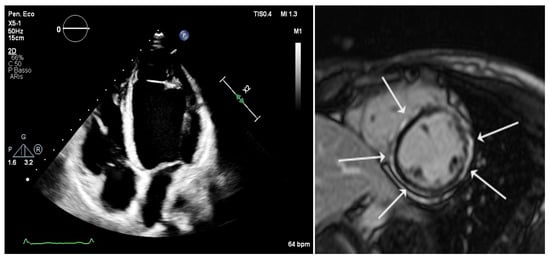

Arrhythmogenic cardiomyopathy (ACM; MIM #107970) is a primitive heart muscle disease characterized by progressive myocardial loss and fibrosis or fibrofatty replacement, predisposing patients to ventricular arrhythmias, sudden cardiac death, and heart failure. Despite advances in imaging and genetics, early diagnosis remains challenging due [...] Read more.

Arrhythmogenic cardiomyopathy (ACM; MIM #107970) is a primitive heart muscle disease characterized by progressive myocardial loss and fibrosis or fibrofatty replacement, predisposing patients to ventricular arrhythmias, sudden cardiac death, and heart failure. Despite advances in imaging and genetics, early diagnosis remains challenging due to incomplete penetrance, variable phenotypic expressivity, and the fact that fatal arrhythmic events may often occur in the early stages of the disease. In this context, the identification of reliable biomarkers could enhance diagnostic accuracy, support risk stratification, and guide clinical management. This narrative review examines the current landscape of potential and emerging biomarkers in ACM, including troponins, natriuretic peptides, inflammatory proteins, microRNAs, fibrosis-related markers, and other molecules. Several of these biomarkers have demonstrated associations with disease severity, arrhythmic burden, or structural progression, although their routine clinical utility remains limited. The increasing relevance of genetic testing and non-invasive tissue characterization—particularly through cardiac imaging techniques—should also be emphasized as part of a multimodal diagnostic strategy in which biomarkers may play a complementary role. Although no single biomarker currently meets the criteria for a standalone diagnostic application, ongoing research into multi-marker panels and novel molecular targets offers promising perspectives. In conclusion, the integration of circulating biomarkers with imaging findings, genetic data, and clinical parameters may open new avenues for improving early detection and supporting personalized therapeutic strategies in patients with suspected ACM. Full article

Figure 1